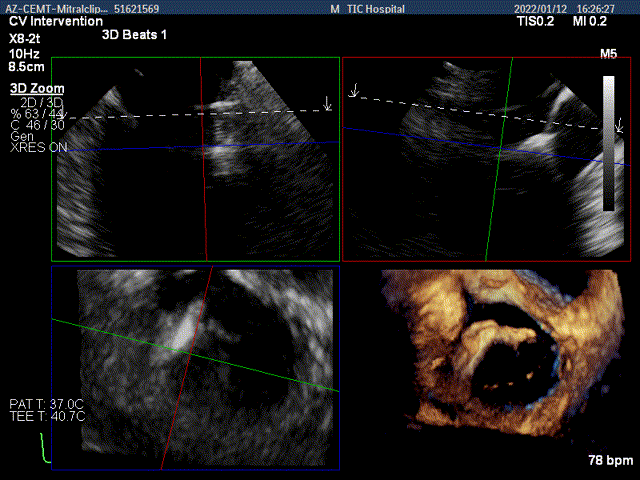

3D MV View:二尖瓣AC区为主(累及部分1区)脱垂并腱索断裂

3D-color MV view:大量返流,主要来源于AC区

Qlab软件勾画估测瓣口面积约:6.89cm2

二尖瓣口平均跨瓣压差:3mmHg

TEE Bicom view:二尖瓣AC区为主(累及部分1区)脱垂并腱索断裂。

Color-view:大量返流,主要来源于AC区